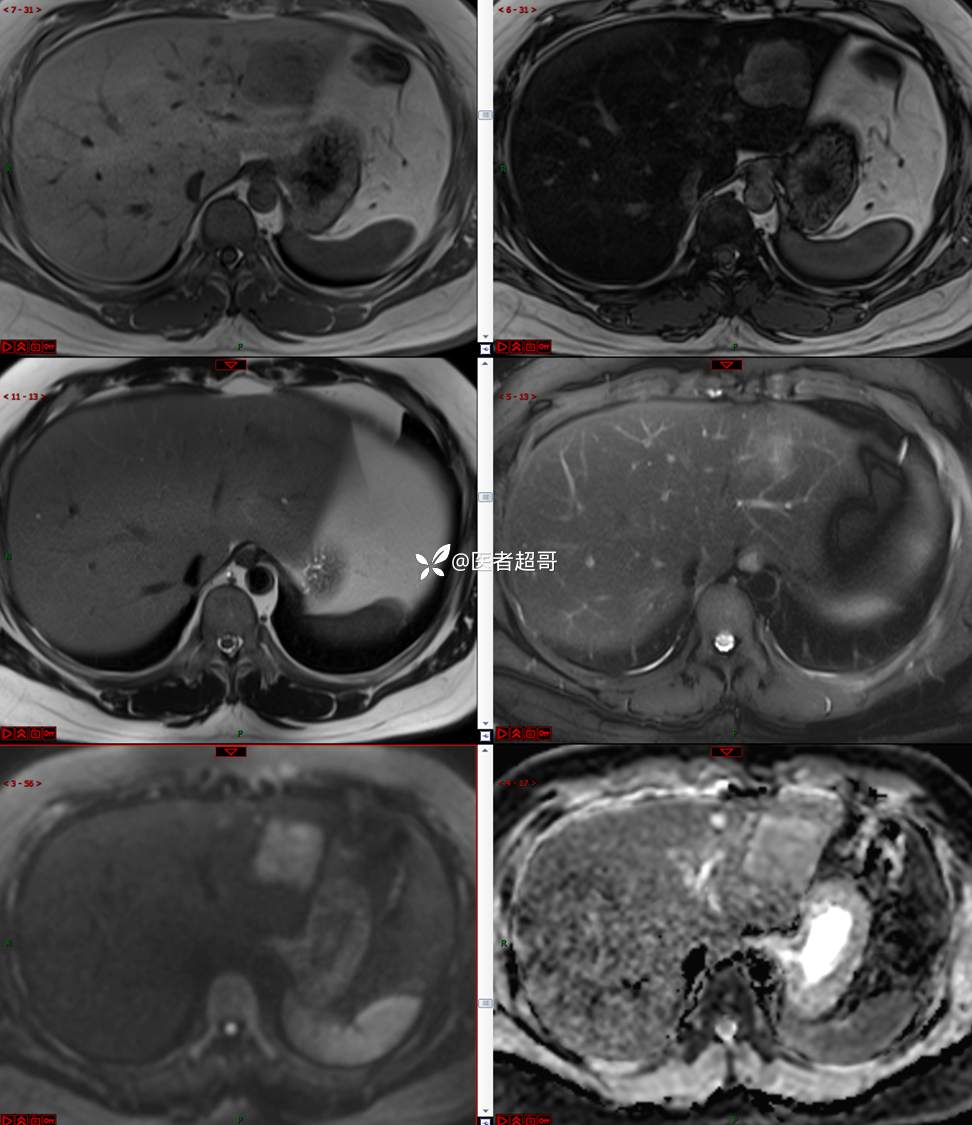

【影诊笔记685】男,31y,发现肝占位性病变5天就诊,请诊断分析,有病理结果!

主 诉:发现肝占位性病变5天。

现病史:患者缘于5天前体检时发现肝占位性病变,未予以特殊处置。现患者为求系统诊治就诊于我院,行普美显提示:肝左叶富血供占位,请结合临床及其他检查,肝多发血管瘤,脂肪肝,肝囊肿,请结合临床。门诊以“肝占位性病变”收入我科。病程中,饮食睡眠可,二便可,近期体重未见明显变化。